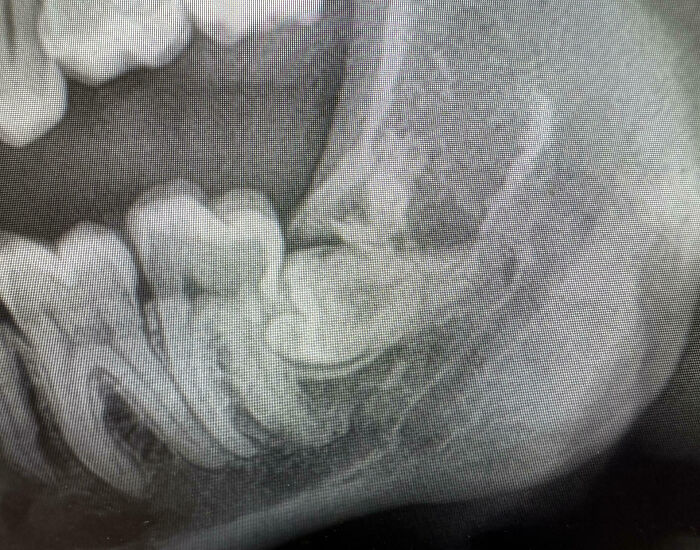

Moj zub múdrosti. Človek by si myslel, že by bolo dosť múdre nerobiť tento typ vecí a vybrať ho von